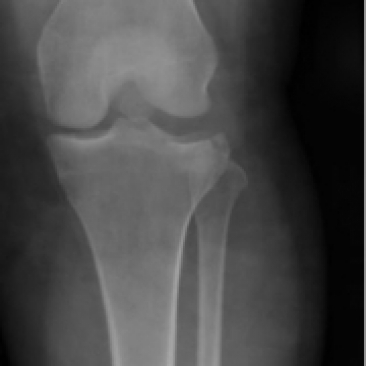

A 40 yo female presents with knee pain after climbing a fence and landing on her left knee. She reports that she was not able to ambulate afterwards. On exam, her left knee is swollen and bruised, distal pulses are intact, limited strength testing because patient reports she cannot bend her left leg at the knee. She has left medial and lateral knee joint line tenderness. Her lower extremity compartments are soft. An xray is shown. What's the diagnosis? Scroll down for answer.

Answer: tibial plateau fracture

- obtain CT if no acute findings on xray and pt unable to bear weight. This patients CT is shown below.